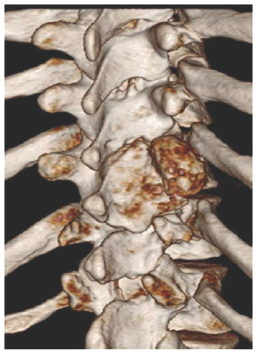

MSCT scan was performed to help in the diagnosis as showen in (Figure 4-7).

Figure 4:

Figure 5:

Figure 6:

Figure 7:

The usefulness of CT and MRI in planning the surgical management of destructive lesions of the spine and evaluating potential spinal instability is emphasized by the case presented.=